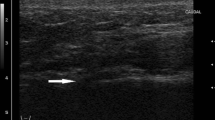

The fusion status of the medial clavicle is assessed following the five-stage scoring system developed by Schmeling et al. [8]. In Fig. 2, five individuals (12–29 years of age) are presented as exemplars for each successive ossification stage; definitions of the features used to describe ossification status in each stage are outlined in Table 1.

Stages 1 to 5 of clavicular ossification as visualized by MDCT in the coronal plane. See Table 1 for associated descriptions of each stage. Note: data is cross-sectional whereby the associated images at each age represent a single individual